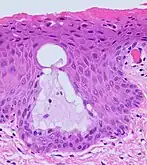

The endocervical mucosa is about 3 mm (0.12 in) thick and lined with a single layer of columnar mucous cells. It contains numerous tubular mucous glands, which empty viscous alkaline mucus into the lumen.[4] In contrast, the ectocervix is covered with nonkeratinized stratified squamous epithelium,[4] which resembles the squamous epithelium lining the vagina.[17]: 41 The junction between these two types of epithelia is called the squamocolumnar junction.[17]: 408–11 Underlying both types of epithelium is a tough layer of collagen.[18] The mucosa of the endocervix is not shed during menstruation. The cervix has more fibrous tissue, including collagen and elastin, than the rest of the uterus.[4]

The squamocolumnar junction of the cervix, with abrupt transition: The ectocervix, with its stratified squamous epithelium, is visible on the left. Simple columnar epithelium, typical of the endocervix, is visible on the right. A layer of connective tissue is visible under both types of epithelium.

Nabothian cysts (or Nabothian follicles) form in the transformation zone where the lining of metaplastic epithelium has replaced mucous epithelium and caused a strangulation of the outlet of some of the mucous glands.[17]: 410–411 A buildup of mucus in the glands forms Nabothian cysts, usually less than about 5 mm (0.20 in) in diameter,[4] which are considered physiological rather than pathological.[17]: 411 Both gland openings and Nabothian cysts are helpful to identify the transformation zone.[15]: 106